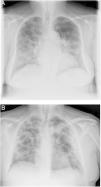

When the radiological image is abnormal, certain common patterns are seen.31 Asymmetrical areas of alveolar or interstitial opacity (patches or diffuse) are identified on simple chest radiograph. The most common pattern is bilateral pneumonia, with subpleural ground glass opacities, poorly defined margins and a slight predilection for the right lower lobe (Fig. 1).

Examples of simple chest radiology of patients with pneumonia in the context of COVID-19.

A) Moderate pneumonia with reticular-alveolar consolidations in the bilateral lower and middle lungs; B) Severe pneumonia showing extensive bilateral involvement with alveolar opacities and a tendency towards consolidation in the periphery of both lungs.

The most characteristic findings on thoracic CT are multiple ground glass opacities with peripheral lung consolidations.32 If these atypical findings are identified (even in asymptomatic patients), the diagnosis of COVID-19 should be considered. CT stratification has been used to assess severity and is the most sensitive diagnostic test, detecting lesions that are sometimes not identified on plain chest radiography. This may be especially relevant in the early identification of cases, for example preoperatively in patients with suspected disease requiring surgery.